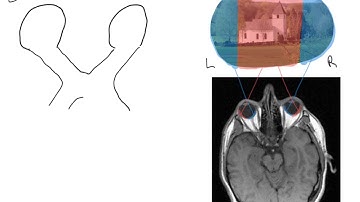

Understanding Bitemporal Hemianopia